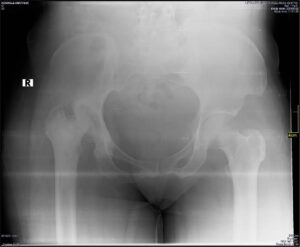

The diagnosis of the 41-year-old followed the X-ray report of her pelvis and femur which shows there is the destruction of her right femoral head, sclerosis, multiple subchodral cysts, and widening of the acetabula rim.

Upon review of the X-ray report, her condition ted with serious pains and discomfort, the doctor, therefore, advised an immediate corrective surgical operation that will cost =N=2,000,000.00 (Two million naira only)

Attached is her X-ray scan and report: